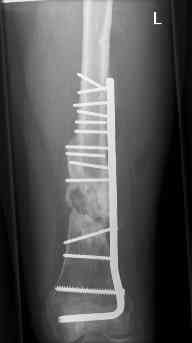

16 yr old boy, high energy motorcycle trauma trauma in July 2005 with:

- hip dislocation + acetabular fracture L

- distal femoral fracture L

- tibial shaft fracture L

- metatarsal fractures L

july 05: LISS femur, LCP plate tibia, double recon. plate post. acetabulum

oct 05: cancellous bone graft femur

aug 06: blade plate + bone graft

nov 06: revision blade plate

feb 07: retrograde nail + bone graft + BMP

may 07: dynamisation nail

sept 07: locking screw removal (max. dynamisation reached)

nov 07: persistant non-union distal femur; other fractures healed uneventfully.